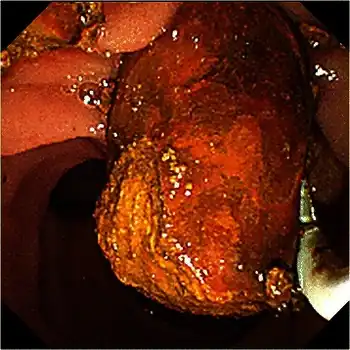

Abdominal ultrasonography of a common bile duct stone -